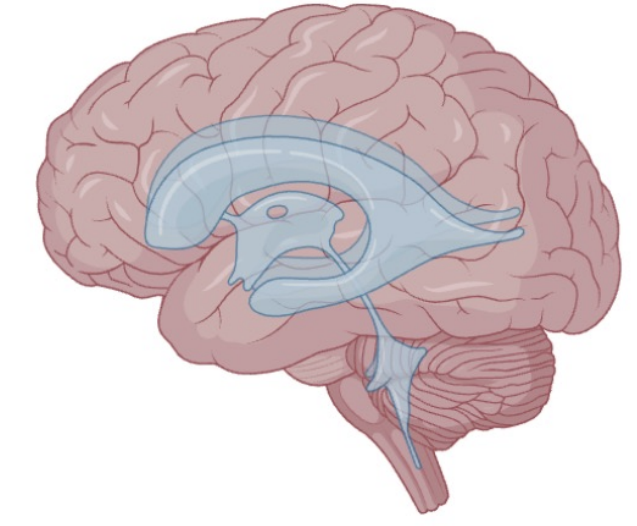

Describe the function of ventricles

4 ventricles that synthesise and circulate CSF through the nervous system

Shock absorbency

Delivers nutrients and flushes cellular waste